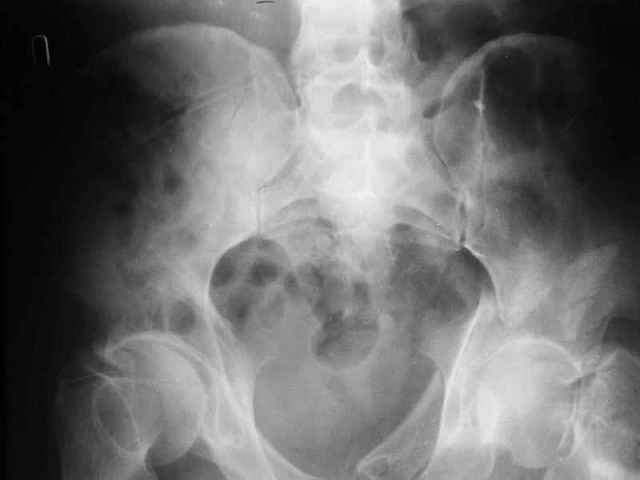

Уважаемые коллеги. Больной был оперирован в одну сессию 25 августа. Сначала на голень наложен спице-стержнвой аппарат. Затем выполнен остеосинтез вертлужной впадины Y-образным доступом. Пришлось дополнительно отсекать вертел. Шейка синтезирована спонгиозными винтами и спицами, вертел - спицами и стягивающей петлей. После операции находился на вытяжении 3 нед. Раны зажили первичным натяжением. Сейчас уже дома. Будет и дальше без нагрузки на левую ногу. Будем наблюдать в динамике. Ждем комментарии.

Перелом шейки был многооскольчатйй очень медиальный, по сути шейку и вертел расколотило об подвздошную кость с кучей мелких фрагментов, вертел был полностьб вовлечен в перелом, головка заподлицо скрывалась в расширенной вертлужной впадине. Качество кости приличное. Остатки дуги Адамса с предварительно проведенными винтами я вколотил в головку и компрессировал винтами - оказалось прочно, но образовался дефект верхнего отдела шейки, который был заплнен фрагментами фиксироваными трансфрактурными спицами - отсюда пучек.

Вертел во время доступа пришлось еще рубить, т.к.

переломы распространялись чересчур дистально.

Отсюда еще пучек спиц.